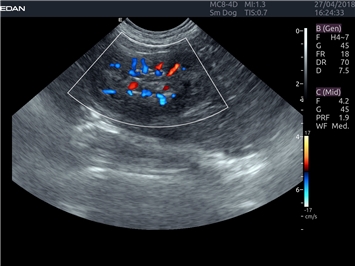

EDAN Acclarix LX4 VET представляет собой профессиональную ультразвуковую систему, специально разработанную для ветеринарных исследований. Сочетание стабильности, высокой производительности и эффективности делает эту систему идеальным выбором для современной ветеринарной практики.

Цветовой допплер:

Да

Трехмерная реконструкция ЦДК: